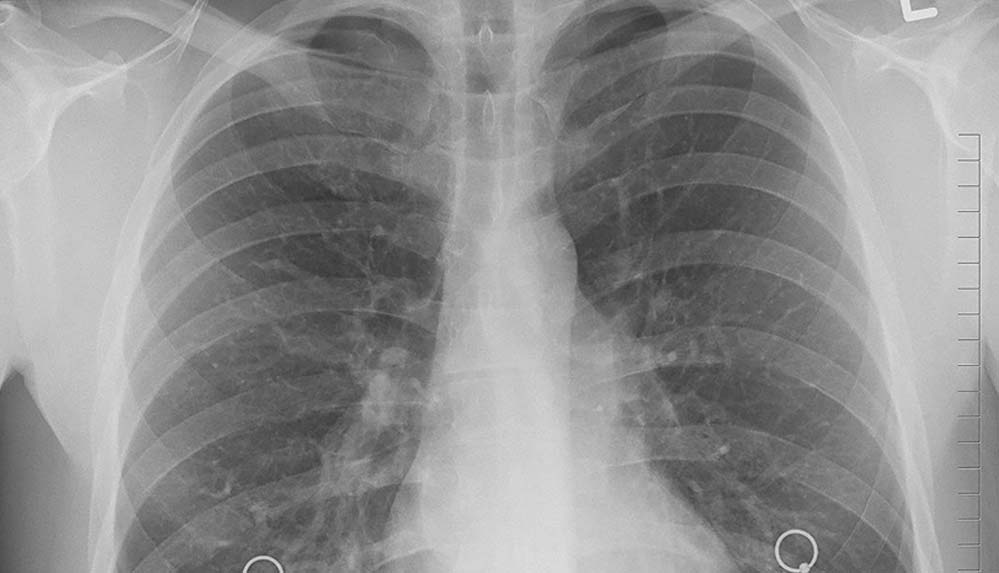

Türk Toraks Derneği Genel Başkanı Prof. Dr. Oya İtil, 1-7 Nisan Ulusal Kanser Haftası dolayısıyla yaptığı yazılı açıklamada, dünyada her yıl 2 milyon kişinin akciğer kanseri tanısı aldığına, 1,8 milyona yakın insanın da bu sebeple yaşamını kaybettiğine dikkati çekti.

Kanser ölümlerinde ilk sırayı akciğer kanserinin aldığına işaret eden İtil, “Türkiye’de her yıl yaklaşık 35 bin insan akciğer kanseri tanısı alıyor. Ülkemiz, erkeklerde 100 bin kişide 41,7 oranı ile dünyada akciğer kanserinin en çok saptandığı ülkelerden biridir ve akciğer kanserinin en önemli nedeni halen tütün ürünleridir.” ifadesini kullandı.